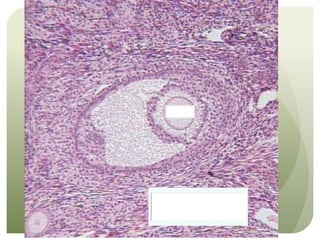

This document appears to be a brief note about an anatomy or histology lesson. It mentions an "Anatomy Bell Ringer #2" and the topic of "Histology," suggesting the document relates to a class that is covering human anatomy and microscopic tissue structures. However, the note indicates there are "Too many things to cover up" in the allotted time, implying the lesson plans to discuss multiple topics but may not have enough time to cover everything.